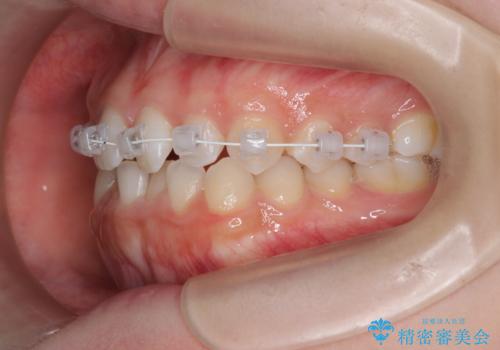

前歯のガタつき・ねじれを治すマウスピース矯正

- 前歯のねじれ、ガタつきを改善し綺麗な歯並びにしたいと希望され来院されました。

マウスピース矯正インビザラインによる矯正治療を計画しますが、マウスピース矯正で治りにくい歯のねじれを事前にワイヤー矯正でしっかりとなおしておくことで矯正治療期間の短縮できるような治療計画を立てます。

マウスピース矯正を始める前にワイヤー部分矯正を行ったことで改善のしにくい歯のねじれをしっかりと治すことができました。